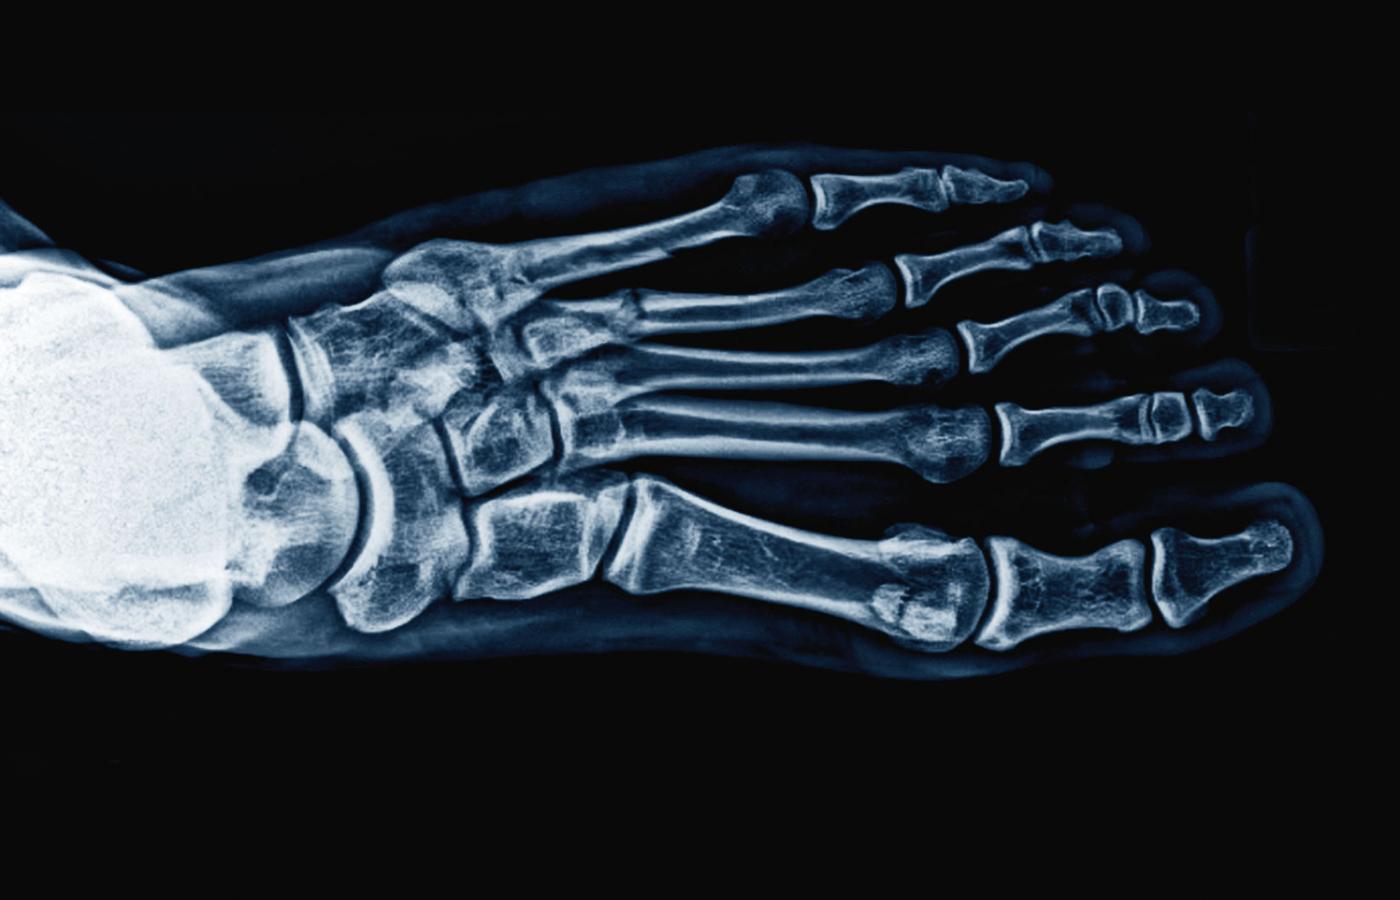

Skręcenie stawu skokowego.Lech Mazurczyk/Polityka Skręcenie stawu skokowego.

Cała kończyna dolna od miednicy do stopy tworzy łańcuch biomechanicznych powiązań. Ten staw budują widełki utworzone przez kość piszczelową i strzałkową (popularnie nazywane kostkami), które obejmują kość skokową. Więzadła łączą je ze sobą, stabilizując staw i pozwalając na ruch. Dodatkową stabilizację zapewniają mięśnie, które poza napędzaniem ruchu reagują na sytuacje niebezpieczne. W tej części odbywa się zginanie grzbietowe i podeszwowe, czyli ruch pozwalający na chodzenie i bieganie. Druga część stawu łączy kość skokową z piętową i pozwala na ruchy na boki oraz dostosowanie stopy do nierówności podłoża. Funkcją stopy i stawu skokowego jest więc stabilne podparcie, amortyzacja oraz adaptacja do nierówności.